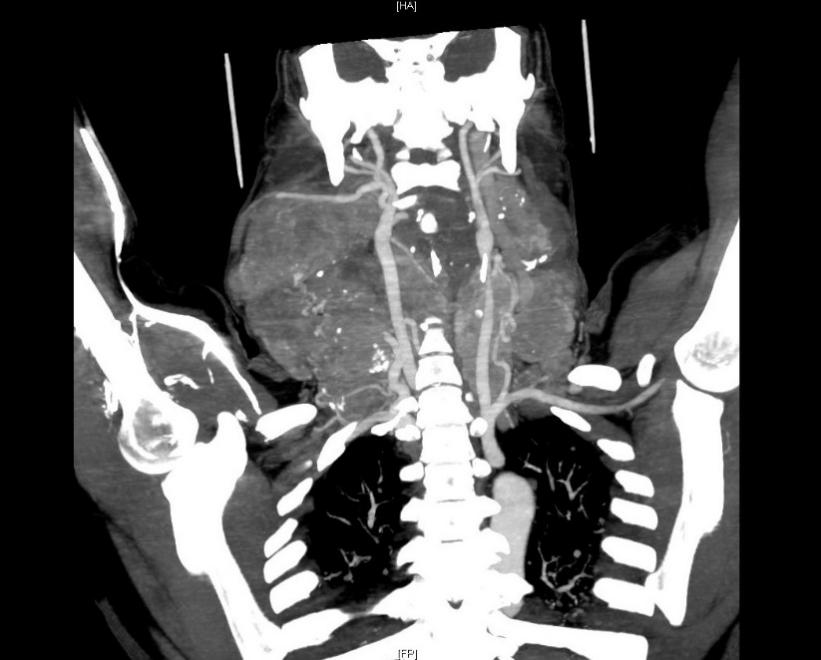

入院后经过超声及CT检查,黄晓明教授团队发现何女士的巨大甲状腺肿物已向下进入胸骨后方,压迫气管,并将喉推向一侧。甲状腺细针穿刺病理检查提示,甲状腺乳头状癌伴颈部淋巴结转移,最大直径超过20厘米,部分肿物已经探及颈后区和锁骨下方,术前胸部CT提示双肺多发转移瘤(见下图)。